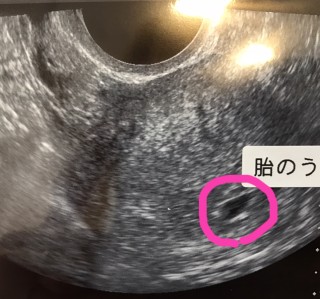

5w0dでたいのうが確認できました!とても小さくて不安でしたが、先生に「順調ですよ」と言ってもらえてほっとしました!

小さな黒い点が赤ちゃんです。無事にすくすく育ってます

胎嚢(約9mm)確認できました。 現在5週0日目☆ 先生から非常に順調ですと言われて嬉しかったです。スクスク育ってほしいです!